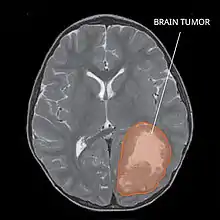

Primitive neuroectodermal tumor of the central nervous system in a 5-year-old

Magnetic resonance image of PNET

Several analysis can be used to determine the presence of the disease. Physical examinations showing papilledema, visual field defects, cranial nerves palsy, dysphasia, and focal neurological deficits are evidences for possible tumor.[2] PNETs can also be spotted through computed tomography (CT) and magnetic resonance imaging (MRI).[2] In images produced by MRIs, an irregular augmentation among a solid mass will indicated the presence of tumor.[3] However, the results of MRIs are usually ambiguous in defining the presence for this specific tumor.[2] In CT scans, the presence of PNETs will be indicated by an elevated density and an increase in volume of the brain.[2] The CT scan can also show calcification,[3] which is present in 41-44% of PNET cases.[2] Since the tumor can be replicated in other parts of the nervous system through the cerebrospinal fluid (CSF), a CSF analysis can also be conducted.[2] A spinal MRI is a fourth type of analysis that is useful in investigating the level of tumor propagation to the spinal cord.[2]